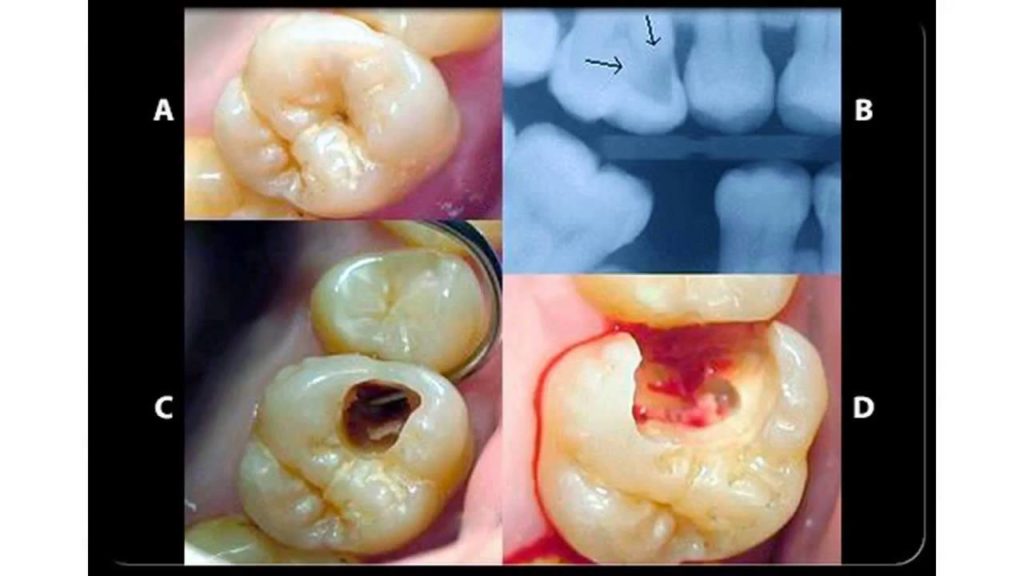

home Procedures Common Dental Problems and Procedures Common Dental Problems and Procedures By dentists Posted in Procedures Posted on May 31, 2017